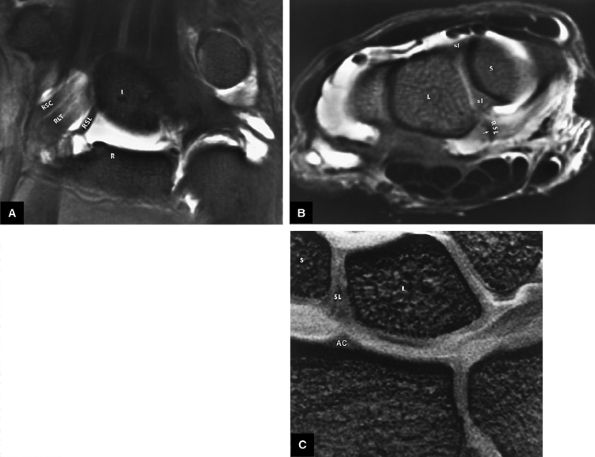

FIGURE 10.67 ● Anatomy of the radioscapholunate (RSL) and radioscaphocapitate (RSC) ligaments. (A) The RSL ligament represents a neurovascular structure extending from the distal radius into the scapholunate articulation. This ligament, which has also been referred to as the ligament of Testut and Kuenz, is located volar to the intrinsic scapholunate ligament. RLT, radiolunotriquetral ligament; L, lunate; R, radius. FS coronal T1-weighted arthrogram. (B) RSL (arrow) extending to the scapholunate interval between the scaphoid (S) and lunate (L). Note the relative volar location of the extrinsic RSL to the intrinsic scapholunate ligament. sl, dorsal and volar portions of the intrinsic scapholunate ligament. FS axial T1-weighted arthrogram. (C) At the level of the distal radius, the normal articular cartilage (AC) ridge between the scaphoid fossa and lunate fossa demonstrates a triangular appearance and is seen in the same plane as the intrinsic scapholunate ligament. This articular cartilage ridge should not be mistaken for a site of ligamentous attachment. Spoiled GRASS (SPGR) coronal image with a 4-cm FOV and 1-mm slice thickness.

a straight course or minimally convex radial border directed toward the scapholunate interval. The radioscapholunate ligament does not have the striations previously described for the radioscaphocapitate and radiolunotriquetral ligaments on coronal images. The proximal attachment of the radioscapho-lunate ligament should never be confused with the normal articular cartilage ridge that separates the scaphoid and lunate fossa of the distal radius. This articular cartilage ridge has a broad-based attachment to the distal radius.